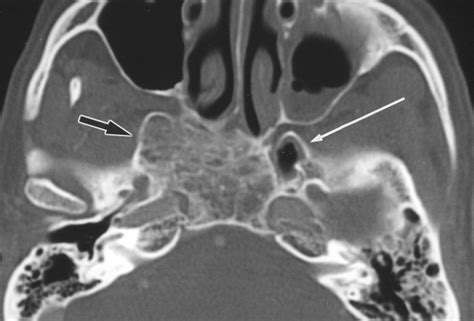

Computed Tomography (CT)

CT scans provide detailed images of the bony structures of the skull, making them ideal for evaluating fractures or bony tumors involving the lesser wing of sphenoid. CT scans can also help identify any displacement or narrowing of the optic canal or superior orbital fissure.

Magnetic Resonance Imaging (MRI)

MRI is particularly useful for evaluating soft tissue structures, such as the optic nerve, cranial nerves, and blood vessels. MRI can help identify tumors, inflammation, or other pathologies affecting the lesser wing of sphenoid and its associated structures.

Radiological Anatomy of the Lesser Wing of Sphenoid

Understanding the radiological anatomy of the lesser wing of sphenoid is crucial for accurate diagnosis and treatment planning. The following table summarizes the key radiological features of the lesser wing of sphenoid:

Structure Radiological Features

Optic Canal Bony canal transmitting the optic nerve and ophthalmic artery. Visible on CT and MRI.

Superior Orbital Fissure Gap between the lesser and greater wings of the sphenoid bone. Visible on CT and MRI.

Lesser Wing of Sphenoid Thin, flat structure forming part of the anterior cranial fossa and the roof of the orbit. Visible on CT and MRI.

These radiological features are essential for evaluating the lesser wing of sphenoid and its associated structures in various clinical scenarios.